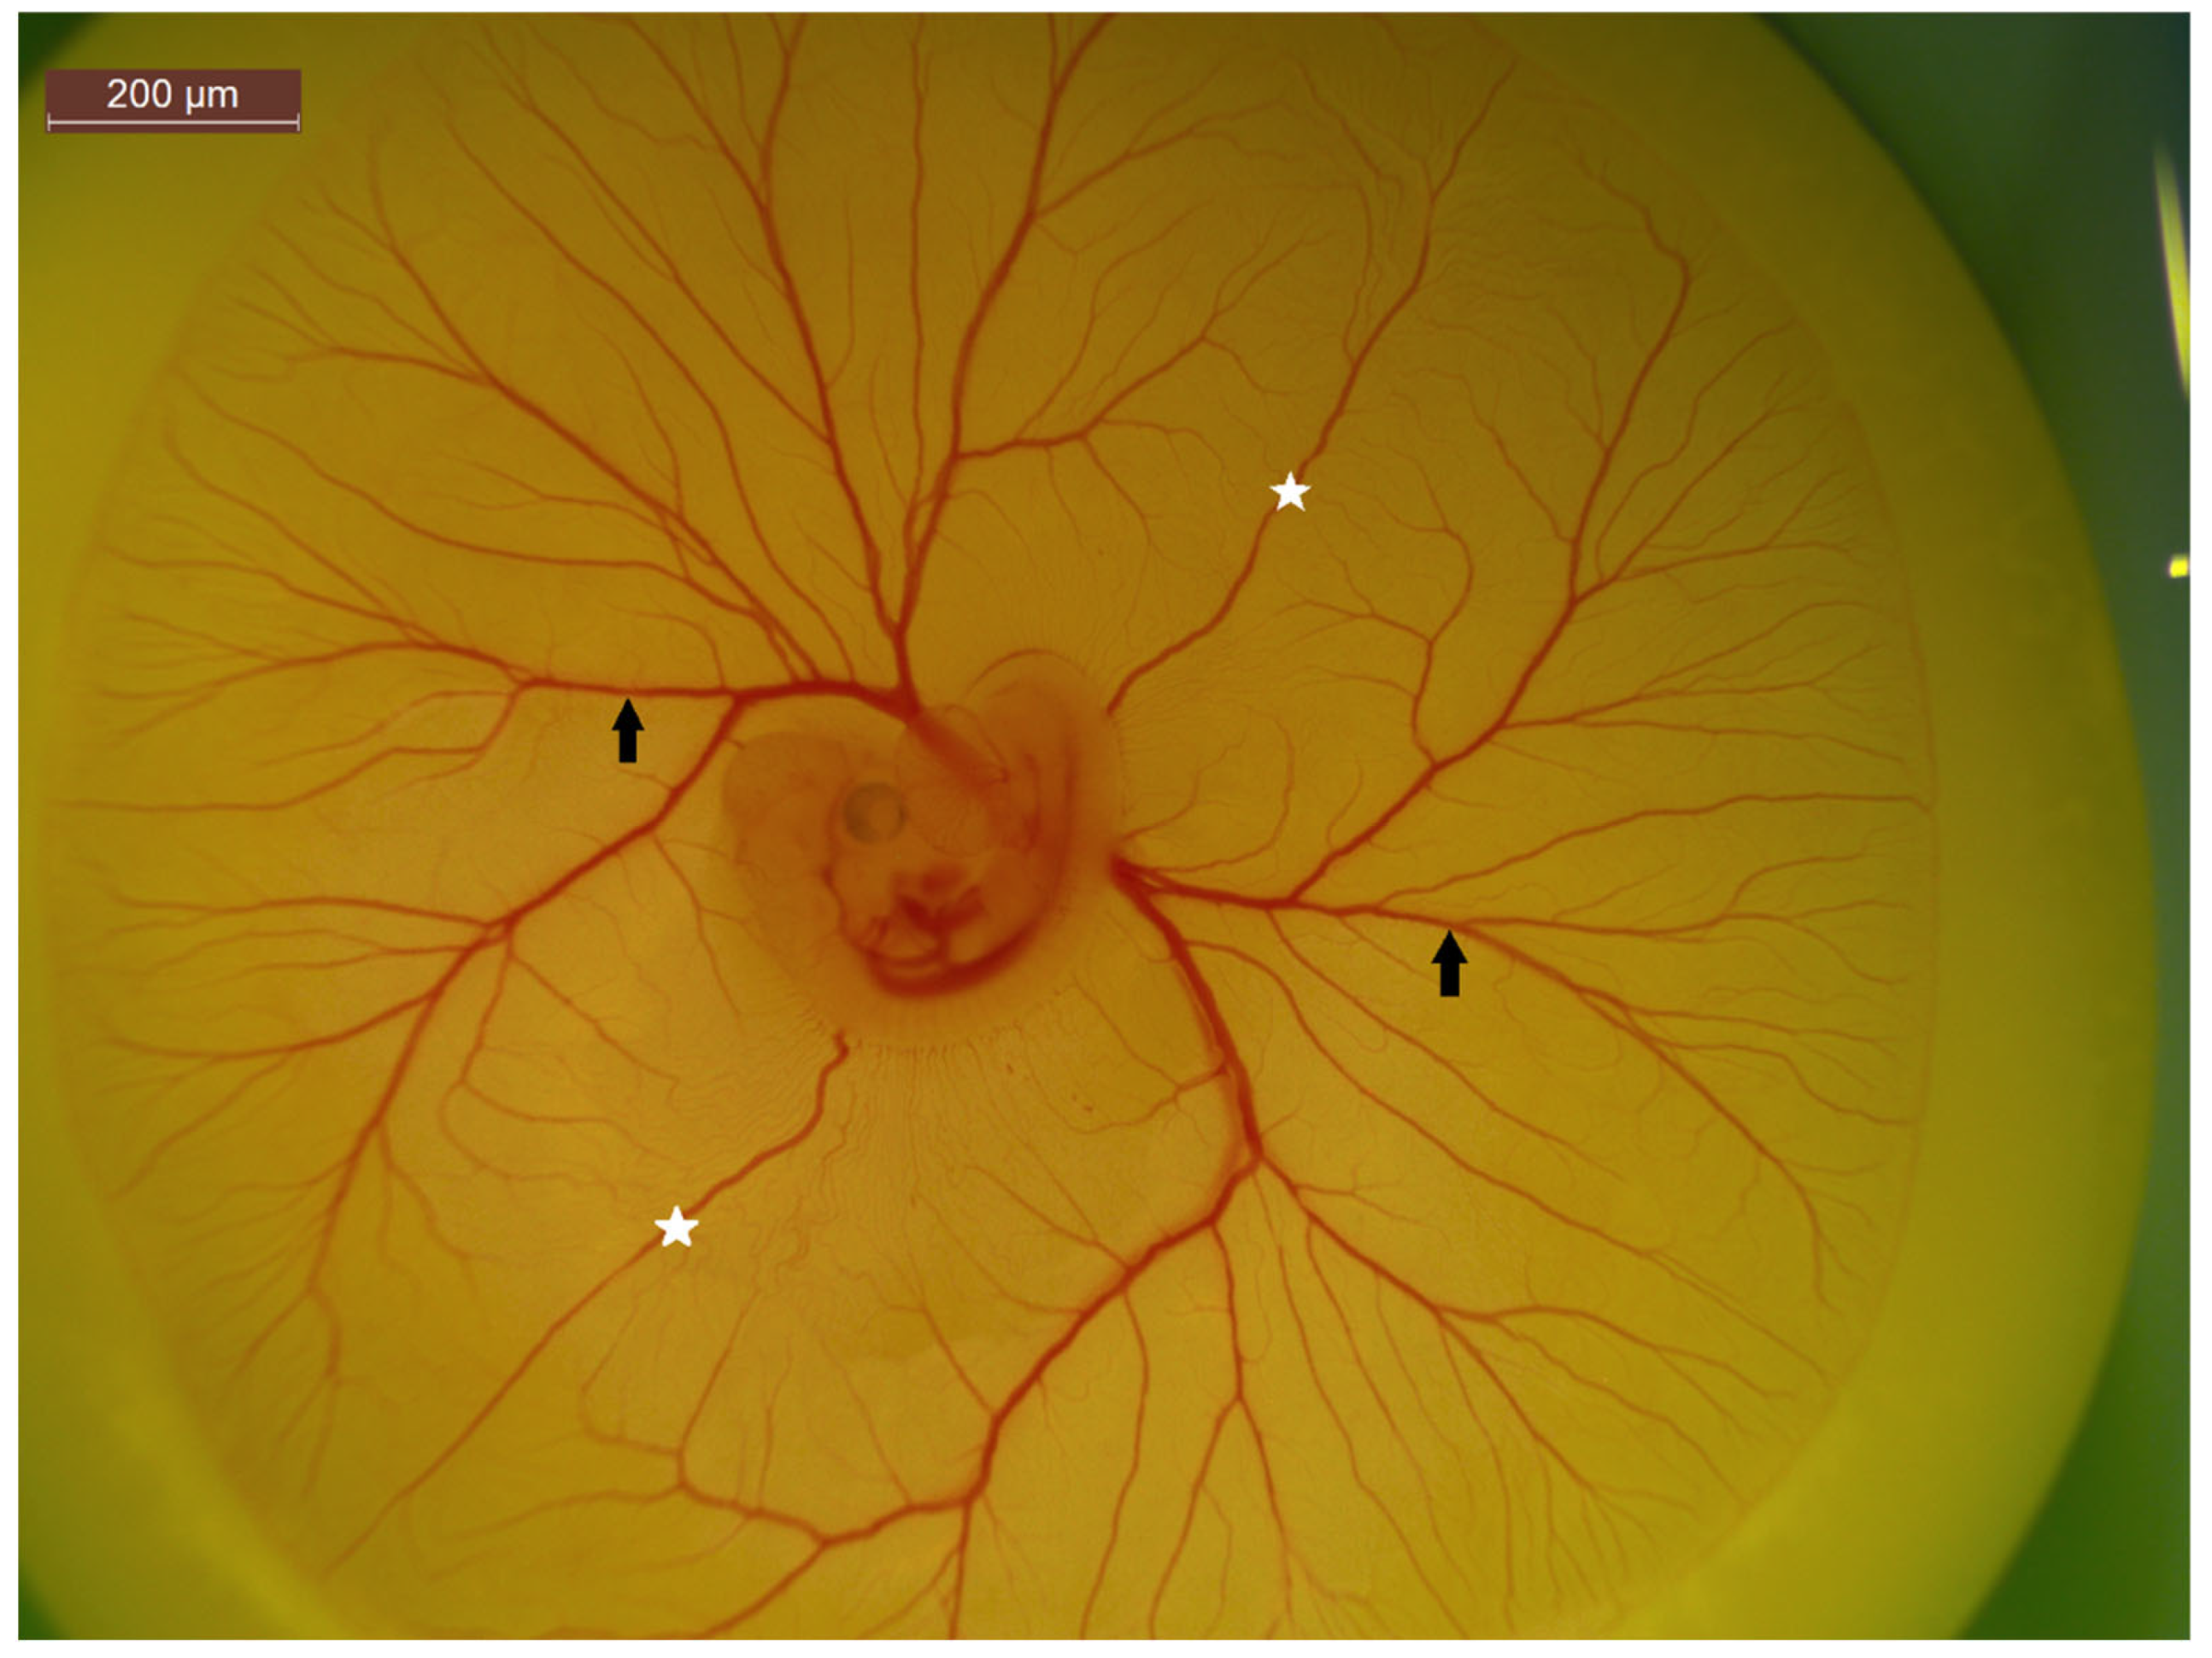

Figure 1.

Image of 7-day-old chick embryo with associated chick chorioallantoic membrane (CAM) and its vast vascular network of capillaries, veins and arteries visible. Image taken at 25× magnification.

Figure 4.

A 5-day-old chick embryo highlight CAM vasculature. The white stars represent anterior and posterior vitelline veins, while the black arrows indicate vitelline arteries and veins. The non-branching nature of the vitelline veins make it an ideal location for injections.